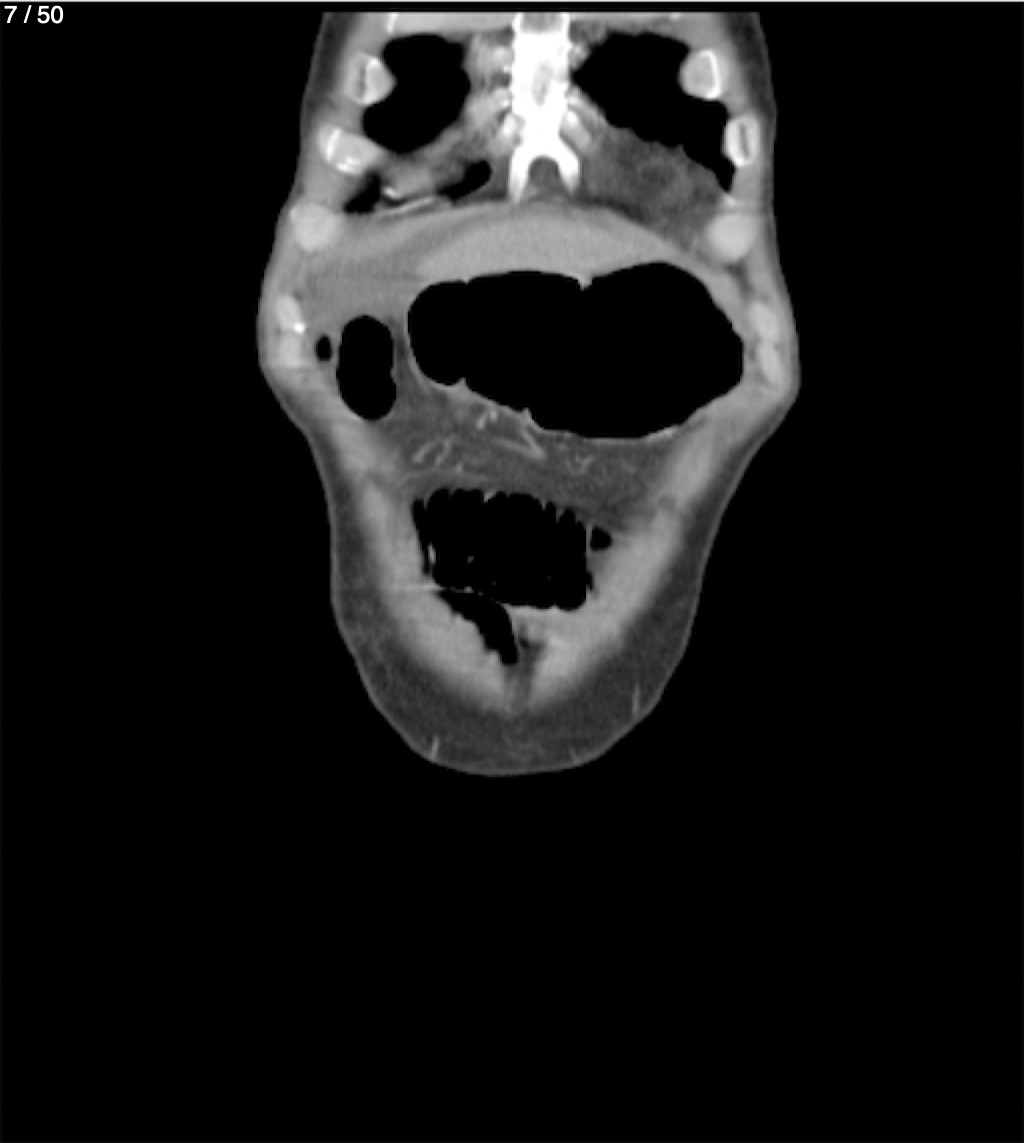

Alonso Victorio Ruiz 62A - T.C Abdomen Syc